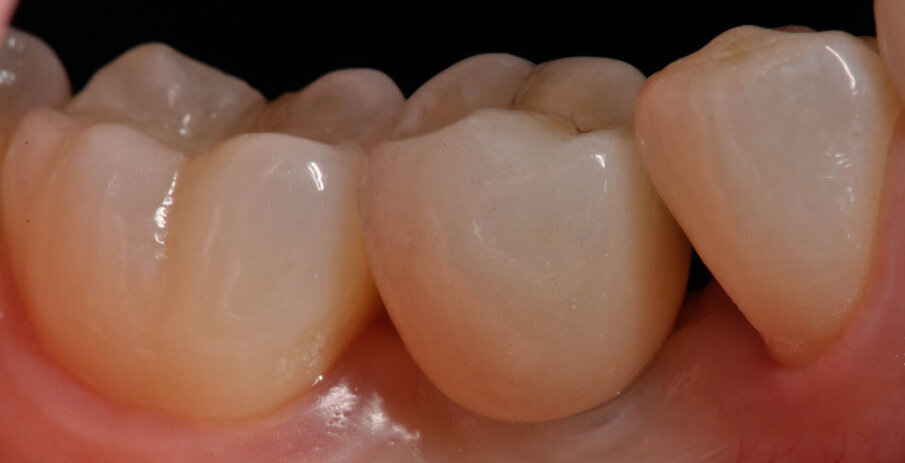

Fig. 15_Lo strato superiore realizzato in Vita Trilux Forte (sx).

Fig. 16_Lo strato superiore realizzato in Vita Trilux Forte (dx).